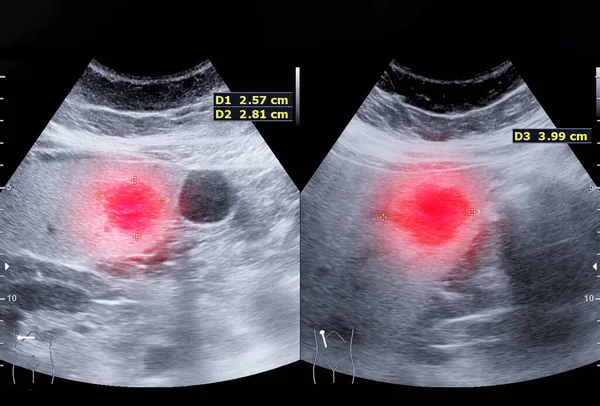

USG Both Breast Scan

Ultrasound (USG) Both Breast Scan is a specialized imaging examination used to evaluate both breasts for any abnormalities or changes in breast tissue. This non-invasive procedure employs high-frequency sound waves to create detailed images of the breast tissue, including the mammary glands, ducts, and surrounding structures. By examining both breasts simultaneously, radiologists can compare any differences in breast tissue and identify any suspicious findings such as masses, cysts, or areas of increased vascularity. USG Both Breast Scan is commonly used as a supplementary imaging tool alongside mammography or as a primary screening method for women with dense breast tissue or those at higher risk for breast cancer. It plays a crucial role in early detection, diagnosis, and monitoring of breast conditions, ultimately contributing to better outcomes and management of breast health.